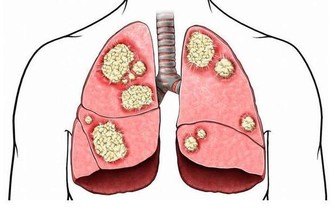

當一定量的內臟脂肪其實是人體必需的,因為內臟脂肪圍繞著人的臟器,對人的內臟起著支撐、穩定和保護的作用。然而,當內臟脂肪堆積過多時,一方面就會形成水桶腰、將軍肚等造成身材不美觀的問題;另一方面,內臟長期堆積過多脂肪會影響消化功能,導致內分泌紊亂,還增加了患高血脂、高血壓、脂肪肝等疾病的機會,下面就跟小編一起詳細瞭解吧!

內臟脂肪囤積過多無法自然離開身體,嚴重影響消化功能,便秘現象也就隨之而來了。